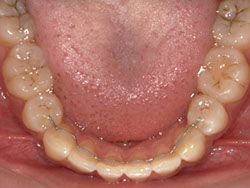

1期治療でスケルトンタイプの拡大装置で歯列拡大後、上下第一小臼歯を抜歯して口元もキレイになりました。

矯正前

矯正中

矯正終了後